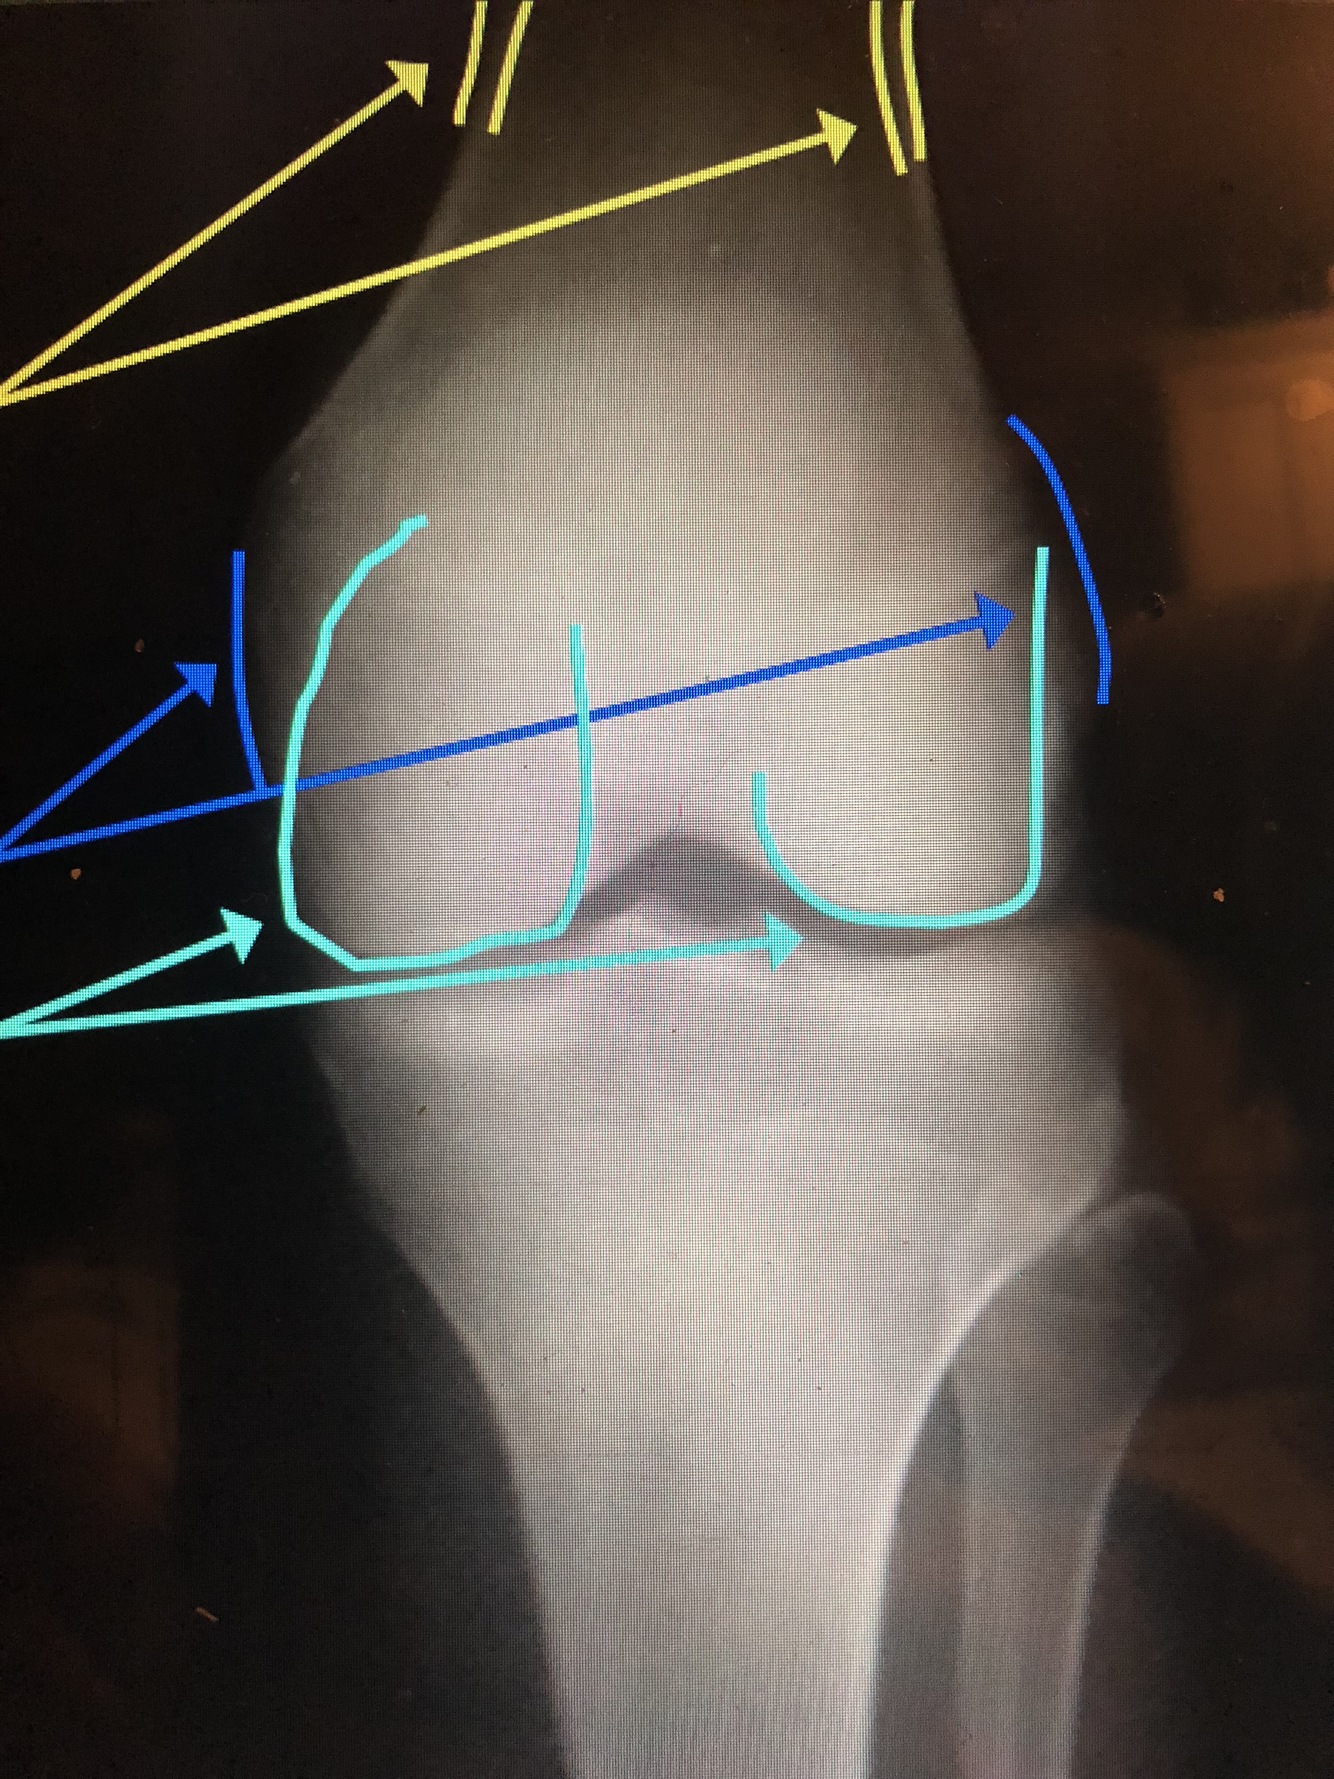

What is the light blue line?

Lateral Femoral Condyle

•Usually projects more proximally and is smaller

What is the yellow line?

Medial Femoral Condyle

•Usually is larger and is projected more distally

What is the dark blue lines?

Epicondyles (med. & lat.)

what is the light blue lines?

Femoral Condyles (med. & lat.)

What are the yellow lines?

Supracondylar Ridge/Line (med. & lat.)

Adductor Tubercle

What is the dark blue line?

Intercondylar Notch

What is the green line?

What is the orange line?